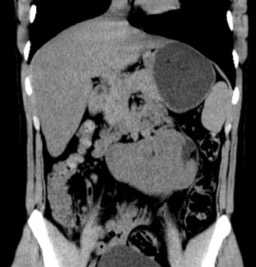

(Слева) В 29 нед. обнаружена правая эктопическая почка (калиперы) вблизи правой общей подвздошной артерии Левая почка расположена нормально (не показана).

(Справа) Для обнаружения тазовой почки при пустом почечном ложе прибегают к ЦДК. В данном случае левая почечная артерия расположена нормально, а от аорты вблизи бифуркации отходят две правые почечные артерии.